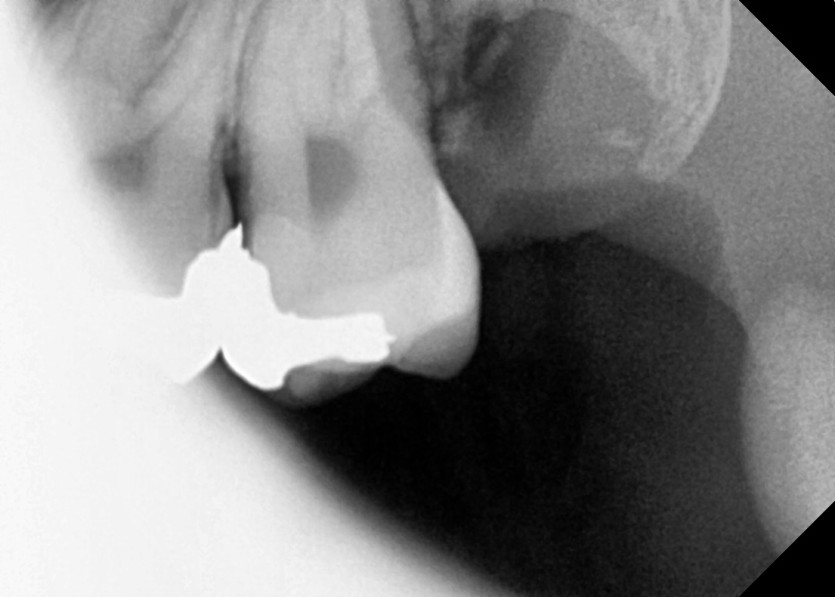

#28,38 사랑니 발치

구강 외과 전문의가 당일 발치했습니다.